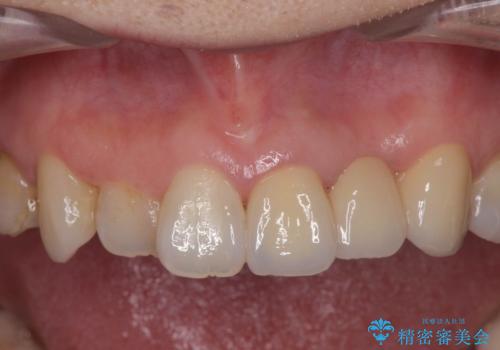

精度、周囲の歯の色調にこだわったオールセラミックブリッジを作製し、しっかりと機能・審美性を改善することができました。